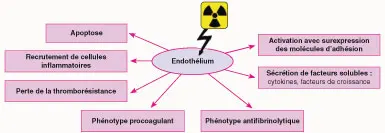

Histopathologie

Les effets des radiations ionisantes sur ce système lymphatique vont être assimilés aux principaux effets obtenus sur l’endothélium vasculaire, à savoir la mort cellulaire radioinduite, l’activation du système de coagulation, l’activation endothéliale et la sécrétion de cytokines ou de facteurs de croissance (figure 25.2) [3].

Fig25.2

Mort cellulaire radio-induite

Les cellules endothéliales sont considérées comme radiosensibles, ce qui explique cette mort cellulaire après irradiation, intervenant sous deux formes : « mort mitotique » (survenant au moment de la mitose) et « mort apoptique » (en dehors de toute mitose) [4]. Cette mort cellulaire contribue à l’initiation et à la progression des dommages radio-induits.

Activation du système de coagulation

Il s’agit d’un processus physiologique stimulé après irradiation correspondant à une perte de la thromborésistance endothéliale [3]. C’est en relation avec une sécrétion accrue de thrombine ayant une double action :

« Procoagulant » : à terme, cela va être responsable d’occlusions thrombotiques capillaires et d’athérosclérose accélérée ;

Augmentation de la synthèse de matrice extracellulaire (activation des fibroblastes) qui va conduire progressivement à l’apparition d’une fibrose périvasculaire [3].

Activation endothéliale

L’activation de l’endothélium vasculaire après irradiation se traduit par une augmentation de l’expression des protéines d’adhésion, qui participent au recrutement des cellules circulantes, responsables de l’inflammation radio-induite des tissus.

Sécrétion de cytokines ou de facteurs de croissance

Après irradiation, l’intima des vaisseaux va sécréter des facteurs de croissance dérivés des plaquettes, de type PDGF (platelet-derived growth factor), responsable d’une prolifération des cellules musculaires lisses à l’intérieur des capillaires de petit calibre, ce qui, à terme, participe au développement de la fibrose postradique.

Le FGF (fibroblast growth factor) sécrété après irradiation participerait à la prolifération anormale de cellules endothéliales, oblitérant la lumière des capillaires [5]. Le TGF-ß (transforming growth factor) activerait les gènes responsables de la production de collagène au niveau des fibroblastes périvasculaires, participant à la fibrose radio-induite [4].

Pour conclure sur le versant histopathologique, les phases précoces des lésions radio-induites sur le système lymphatique se caractérisent par une réaction inflammatoire importante en relation avec l’altération aiguë de l’endothélium vasculaire.

En ce qui concerne les dommages radio-induits tardifs, ils sont expliqués par l’apparition d’une fibrose périvasculaire en relation avec une accumulation pathologique de matrice extracellulaire, et particulièrement de collagènes fibrillaires.